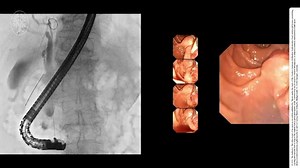

Small-bowel capsule endoscopy and device-assisted enteroscopy for diag

…